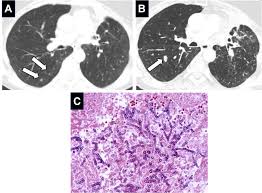

Hemoptysis Evaluation And Management American Family Physician from www.aafp.org Malignant tumors trigger inflammation in surrounding normal lung tissue, and they may obstruct your airways and interfere with normal airflow. This can lead to misdiagnosis as conditions such as irritable bowel syndrome (ibs). In this article they describe a variety of pulmonary conditions that can present with imaging features mimicking those of primary lung cancers. Pneumonia is a lung infection that leads to breathing difficulties and fluid in the lungs. When sarcoidosis affects the lungs, symptoms can mimic idiopathic pulmonary fibrosis including shortness of breath and a dry cough. Pneumonia can be mild and only require a week of treatment before you can. Pneumonia in people with lung cancer. Although slipping from emphysema to copd is usually not a drastic decline in health, early detection of lung cancer is critical for increasing your treatment options and improving your prognosis.

Risk Factors Of Lung Cancer In Chronic Obstructive Pulmonary Disease Download Scientific Diagram from www.researchgate.net Part of the dilemma for doctors is the significant overlap between copd symptoms and lung cancer symptoms. A fungal infection called valley fever, which can cause mild to severe lung problems (including holes in the lungs), is often misdiagnosed because the symptoms can resemble those of the flu or. Copd is a major risk factor for lung cancer. This, in turn, may cause collapse of the air sacs surrounding the tumor. We'll also look at some methods and medical tests commonly used. But, time is of the essence. But recent evidence suggests that copd itself is an independent risk factor for developing lung cancer, separate from any smoking history. By the time the doctor recognizes that treatment has not worked and more testing or a specialist is needed, valuable time is wasted.